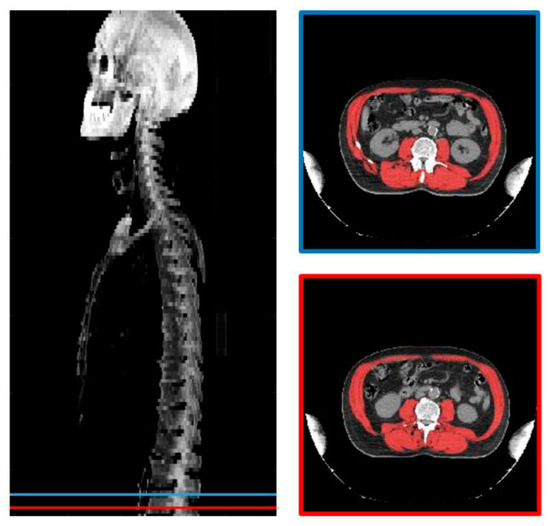

2.2. CT Scan